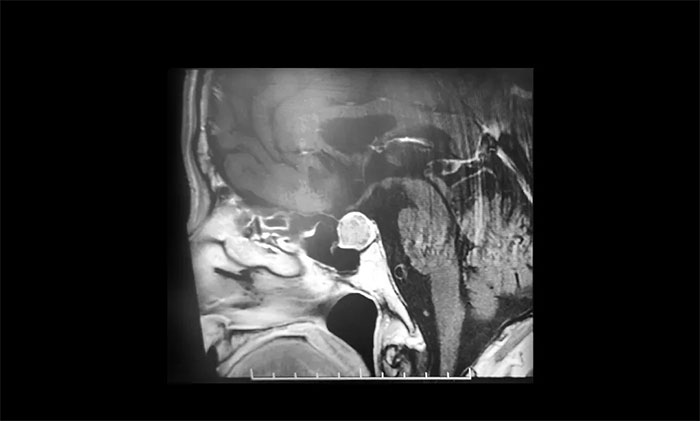

2021年初,王大爺在家人陪同下再到醫(yī)院復(fù)查,鞍區(qū)MRI提示腫瘤較之前增大不少。醫(yī)生表示腫瘤再繼續(xù)長大可能會導致失明,手術(shù)已經(jīng)迫在眉睫,但是手術(shù)風險也隨之增大。為謹慎起見,家人商議決定到上海大醫(yī)院求醫(yī),輾轉(zhuǎn)打聽后,王大爺慕名轉(zhuǎn)入上海藍十字腦科醫(yī)院。

▲ 垂體大腺瘤超蝶鞍生長

入院后,鞍區(qū)MRI平掃+增強顯示:蝶鞍擴大,鞍內(nèi)腫塊樣灶,大小約1.6×1.4×1.2cm,鞍底輕度下陷。神經(jīng)外科6B病區(qū)潘仁龍主任指出,垂體腫瘤超蝶鞍生長,壓迫到視神經(jīng),使患者視物出現(xiàn)異常,一般1-3cm的大腺瘤或大于3cm的巨大腺瘤,都會引起不同程度的視力問題。

李士其教授、潘仁龍主任、吳治群博士會診后指出:從影像學資料上看,發(fā)現(xiàn)瘤體較大,屬于垂體大腺瘤,瘤體占據(jù)鞍區(qū),視神經(jīng)、視交叉受壓,所以需要馬上進行手術(shù)切除,解除壓迫,如任其發(fā)展,很可能會有失明的風險。